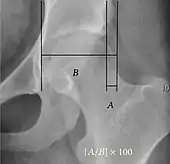

| Reimer's migration index[9] | ![]() |

The percentage of the femoral head that lies outside of the acetabular roof. It is also called the femoral extrusion index. | <25% |

| Tönnis angle | ![]() |